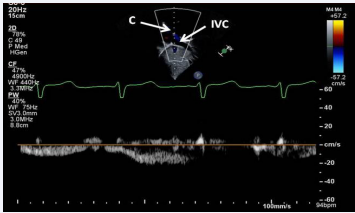

Figure 31 Selected video frame demonstrating low velocity flow between the inferior vena cava (IVC) and the conduit (C) shown in Figure 30, suggesting no evidence for obstruction [69].

Figure 31: Selected video frame demonstrating low velocity flow between the inferior vena cava (IVC) and the conduit (C) shown in Figure 30, suggesting no evidence for obstruction [69].